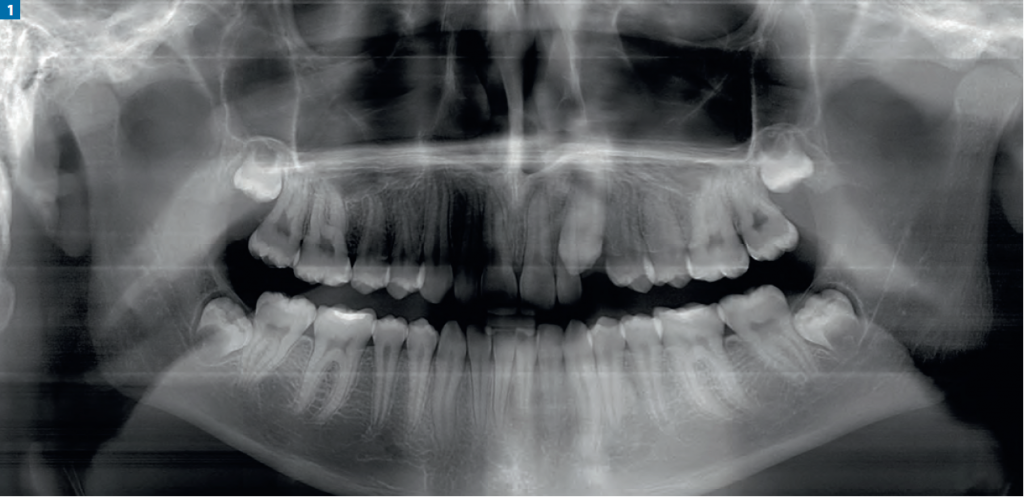

Wprowadzenie zatrzymanego kła górnego do łuku zębowego – opis przypadku

Streszczenie: W artykule opisano zaburzenie o charakterze zatrzymania zęba w szczęce, możliwe przyczyny tego typu nieprawidłowości zębowych oraz sposób postępowania na przykładzie własnego przypadku klinicznego sprowadzenia zęba do łuku zębowego.

Zębem zatrzymanym (łac. retentio dentis) nazywa się ząb (mleczny, stały lub nadliczbowy), którego korzeń jest całkowicie uformowany (w świetle obserwacji klinicznych ząb w prawidłowych warunkach rozpoczyna wyrzynanie, gdy rozwój jego korzenia wynosi ¾ całkowitej długości), otwór wierzchołkowy zamknięty oraz minął już termin jego prawidłowego wyrzynania (powyżej 2 lat). Ząb zatrzymany otoczony kością nazywa się zębem zatrzymanym całkowicie (łac. retentio dentis [...]